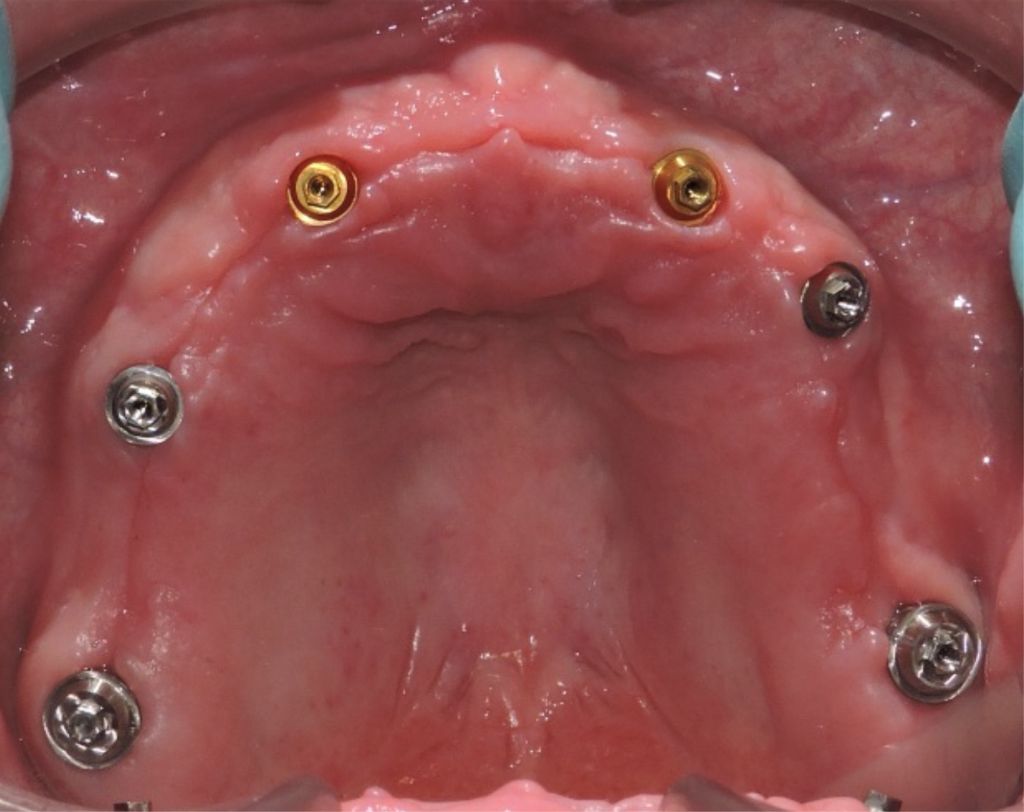

Zirconia Implants

-

After